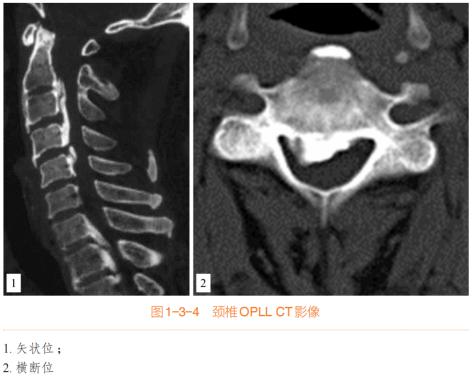

(一)颈椎后纵韧带骨化(OPLL)

骨化物位于椎体后缘,预计经椎间隙无法清除

骨化物累及1 ~ 4个节段(如有准备长节段钛板,亦可治疗长达5 ~ 6个节段的颈椎OPLL)

骨化物累及C2后方或T1后方的高低节段骨化

突出的局限型骨化,预计后路减压效果不佳

对于骨化范围>3个节段、椎管狭窄率>60%、骨化物厚度>5 mm的严重颈椎OPLL患者,直接切除骨化物具有相当难度和风险,手术术式的选择一直是一个争议,此类型患者行ACAF技术的优势更加明显。